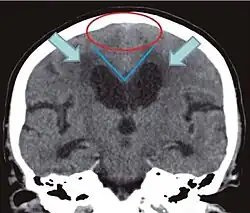

Diagnostisch sollte bei vorliegender klinischer Symptomatik ein CT oder alternativ MRT des Gehirns angefertigt werden. Eine (krankhafte[26]) Erweiterung der inneren[27][26](besonders der Vorder- und Temporalhörner[26]) und äußeren[26] (besonders der Sylvischen Fissur[26]) Liquorräume ist typisch.

Hinweise auf einen Normaldruckhydrozephalus sind:

- disproportionale Erweiterung der äußeren Liquorräume(DESH--„disproportionately enlarged subarachnoid space hydrocephalus“): Weitstellung von Subarachnoidalräumen an lateraler Konvexität, besonders der Sylvischen Fissur und Engstellung der parasagittalen Subarachnoidalräume der oberen Konvexität und der medialen Hirnoberfläche[29]

- Corpus-Callosum-Winkel < 90°[27] / typischerweise 50–80°[30] im koronaren Schnitt[27] senkrecht zur Ac-pc-Ebene[31] auf Höhe der hinteren Kommissur[27]